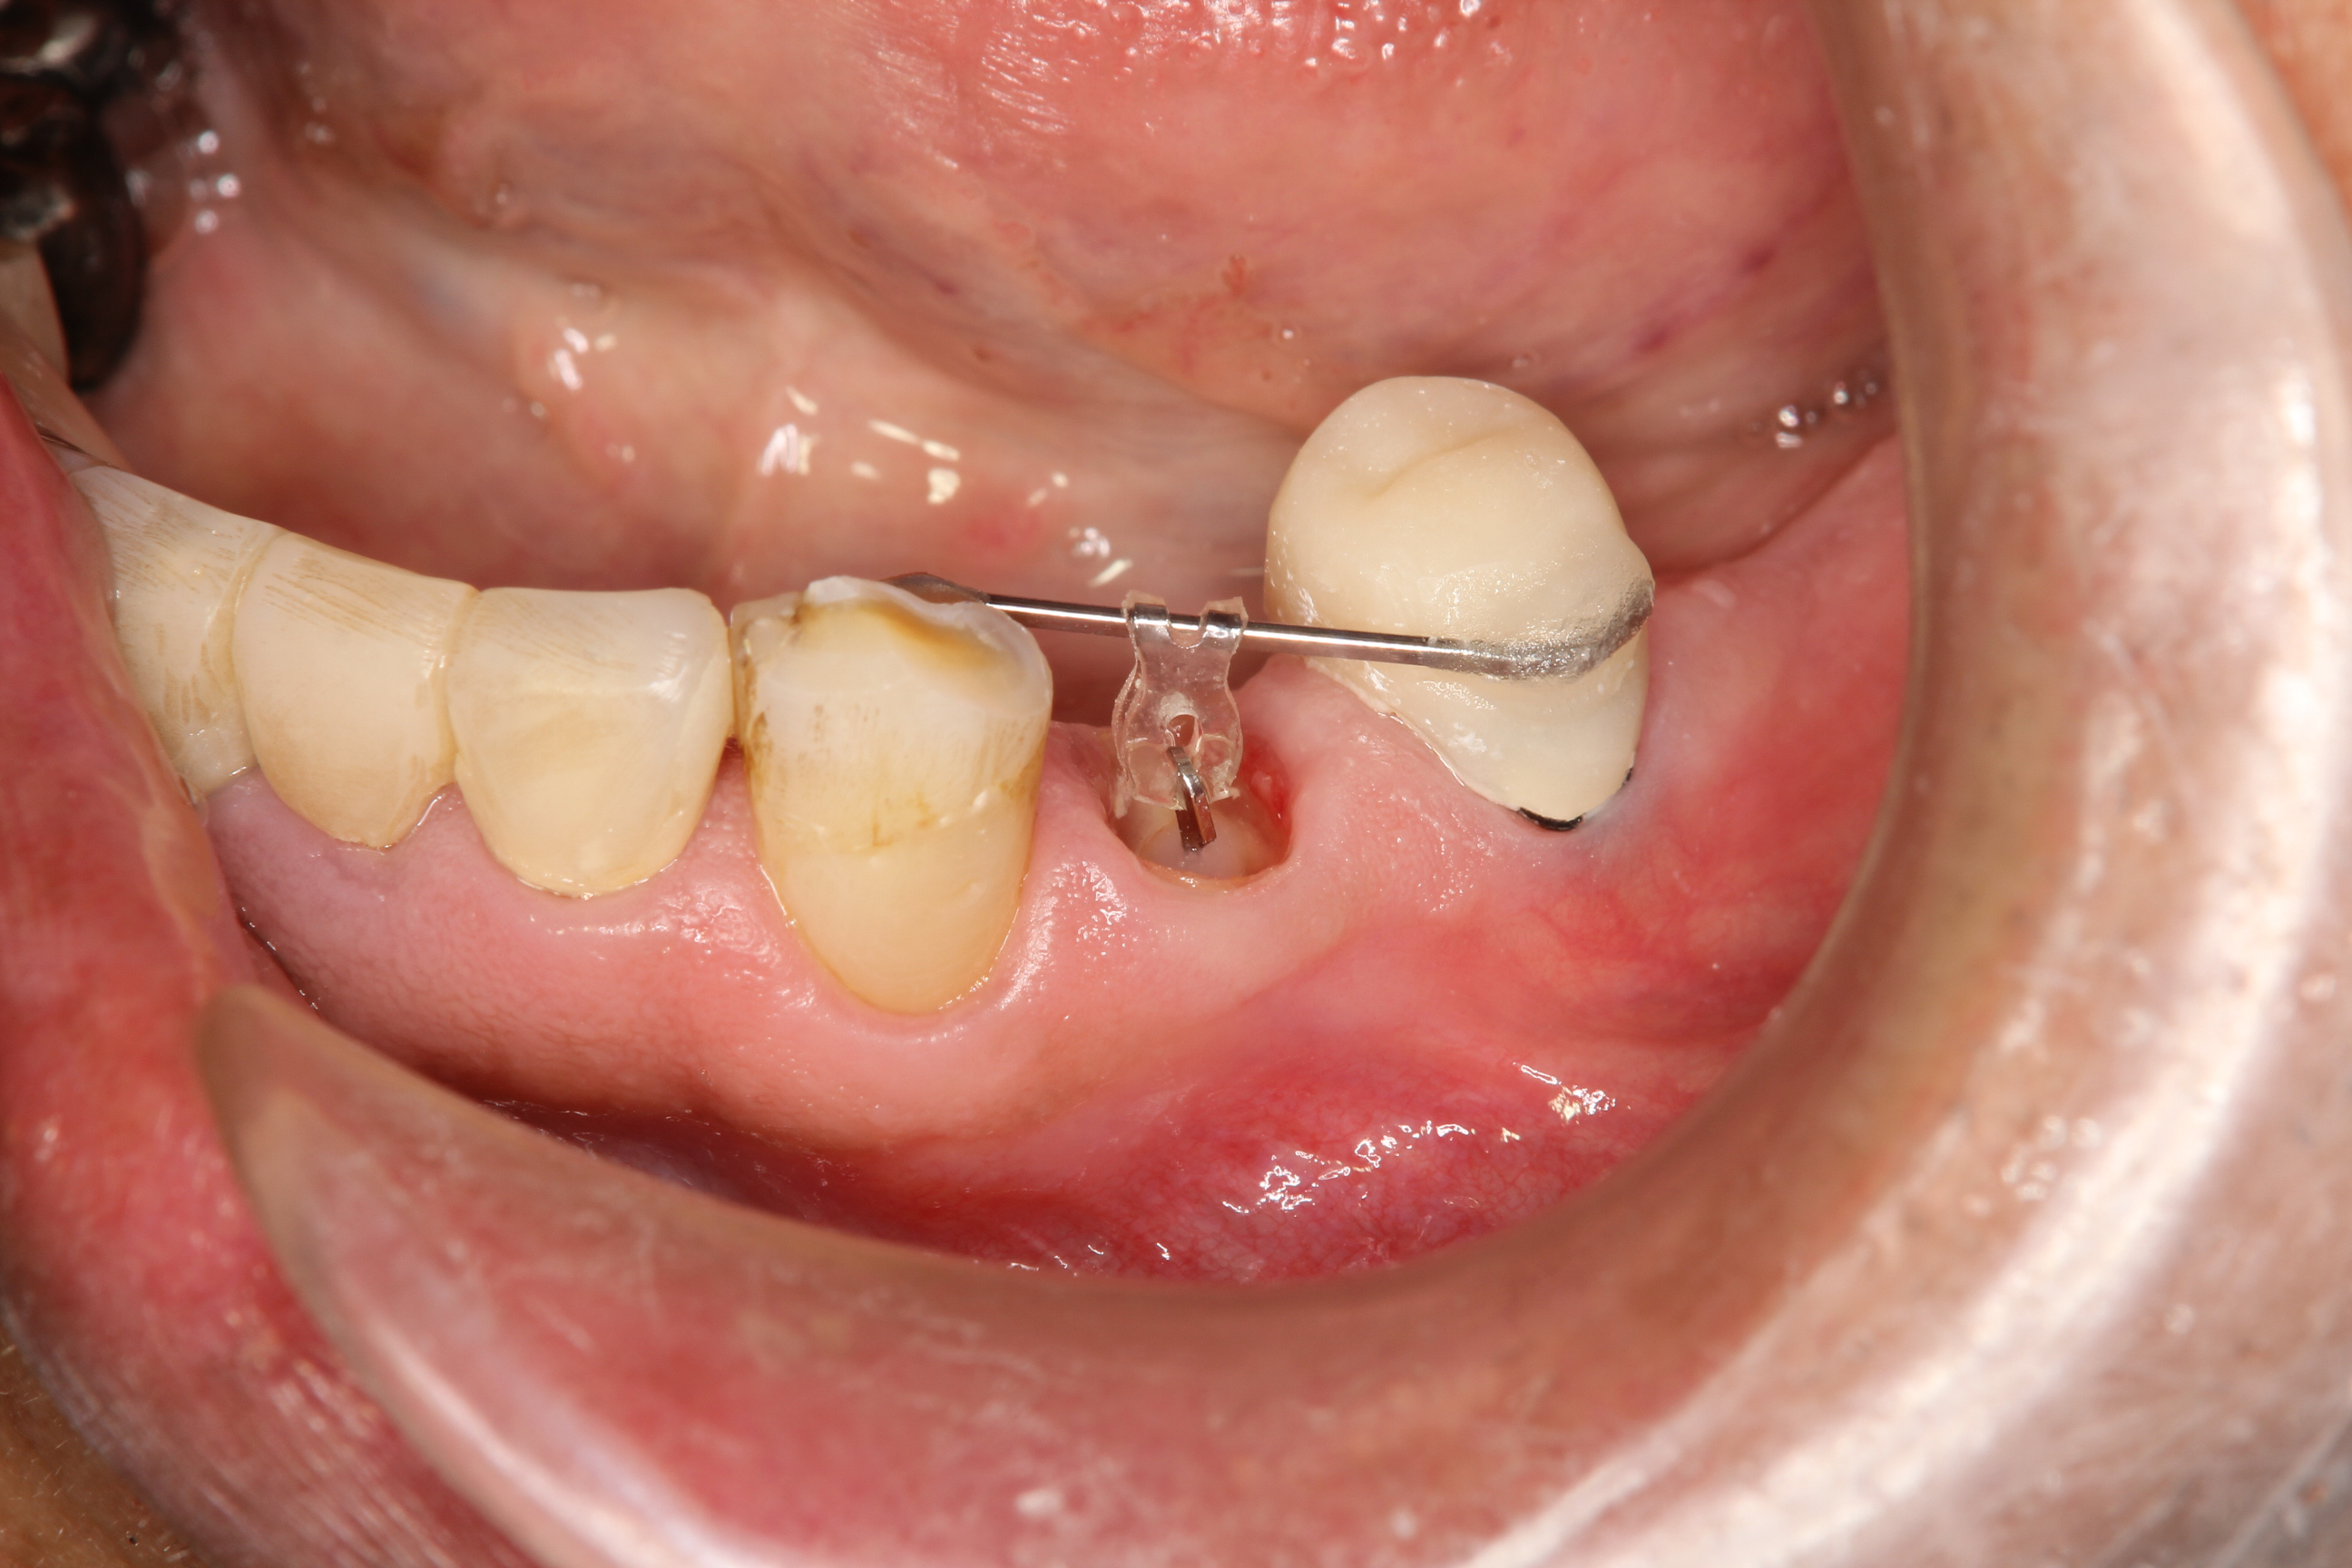

下の写真は、インプラントを埋入し上顎の一部の前歯を除きすべての歯に仮歯を装着した状態です。

また、左下奥歯の欠損に対してはインプラントを埋入することで入れ歯を回避。